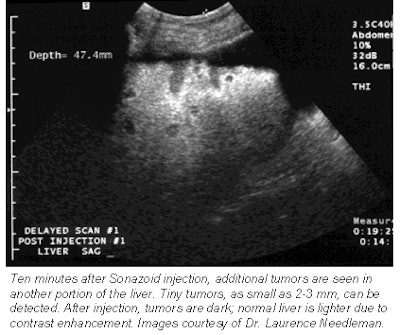

These promising results can be credited to Sonazoid’s long-lasting parenchymal phase, which is a measure of how long the bubbles remain in healthy liver cells before dissipating, said Dr. Laurence Needleman, an associate professor of radiology at Thomas Jefferson University in Philadelphia.

![]() |

"Because the agent stays in the cells for many minutes, even up to one hour after the delivery of the agent, the scans are more specific," Needleman said. "And you’re not under time pressure to perform the scan as soon as you’ve injected the agent, which makes it logistically easy."